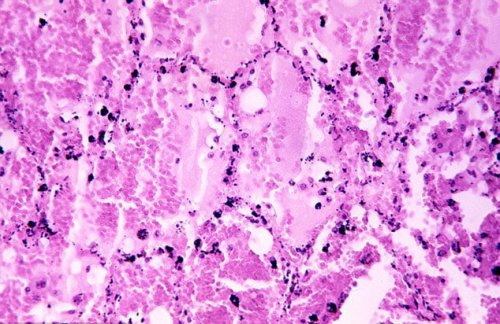

Ученые из Стэнфордского университета разработали простой анализ крови, позволяющий диагностировать туберкулез. С его помощью также можно выделить наиболее заразных пациентов.Простейший анализ крови, аккуратно диагностирующий активную форму туберкулеза, может спасать сотни тысяч жизней каждый год, как считают эксперты. Этот тест делает контролирование болезни более простым и доступным. Каждый год от туберкулеза в разных странах мира умирает полтора миллиона человек, так что эта болезнь считается одной из самых страшных.

Американские исследователи определили выраженность гена, с помощью которой можно отделить пациентов с активной формой туберкулеза от тех, у кого наблюдается латентная форма болезни, либо другие недуги. Эта технология является ответом на призыв Всемирной организации здравоохранения, которая еще в 2014 году обратилась к ученым с просьбой о разработке более совершенных диагностических инструментов для определения активного туберкулеза. В разных странах мира этой болезнью каждый год заболевают 9,6 млн человек.

Туберкулез все еще остается достаточно сложным для диагностики. Традиционные диагностические методы, включая прик-тест с кожей и анализ крови на определение специфического гамма-интерферона не могут отделить пациентов с активной формой туберкулеза от тех, кто более не представляет опасности. Это старые инструменты диагностики, и с их помощью иногда не получается обнаружить наличие туберкулеза у пациентов с ВИЧ. Современные тесты направлены на поиск бактерий, вызывающих туберкулез, по анализу мокроты пациентов, но они также не являются совершенными.